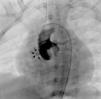

Case 1A 2-year-old asymptomatic boy with a heart murmur underwent an echocardiogram which showed turbulent flow in the subaortic region. He was catheterized and the aortic angiogram revealed a hemodynamically insignificant fistulous tract between the right sinus of Valsalva and the RV (Figure 1).